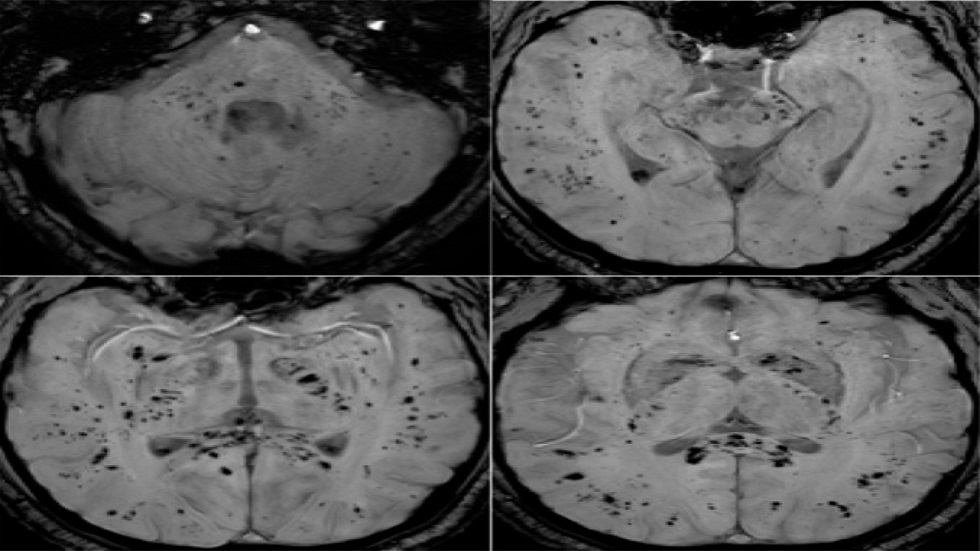

تحليل بالرنين المغناطيسي يكشف تأثير كوفيد-19 المستمر على الدماغ

أظهر تحليل صور بالرنين المغناطيسي أن فيروس كوفيد-19 يترك أثرا لا يُمحى في الدماغ، ويستمر تأثيره حتى بعد التعافي التام.

أظهرت دراسة حديثة أجراها علماء في جامعة غريفيث الأسترالية ونُشرت في مجلة Brain, Behavior, & Immunity Health أن فيروس كوفيد-19 لا يؤثر على الجهاز التنفسي فحسب، بل يترك أثرا ملموسا على الدماغ، ويستمر تأثيره حتى لدى الأشخاص الذين يعتبرون أنفسهم متعافين تماما، حتى إذا لم تظهر عليهم أعراض واضحة.

وأوضح الباحث الرئيسي الدكتور كيران تاباليا أن الفريق استخدم طرق التصوير بالرنين المغناطيسي متعددة الوسائط لدراسة المادة الرمادية والبيضاء في الدماغ، وهي مهمة للذاكرة والوظائف الإدراكية والصحة العامة للدماغ. ووجد الباحثون اختلافات ملحوظة في أنسجة الدماغ وموادها الكيميائية العصبية وشدة الإشارة وبنية الأنسجة لدى المتعافين من كوفيد-19، حتى في حالات الإصابة التي اعتبرت بسيطة.

وأضاف تاباليا: "تبين أن التغيرات في أنسجة الدماغ مرتبطة بشدة الأعراض"، ما قد يفسر مشكلات إدراكية طويلة الأمد مثل تدهور الذاكرة والتركيز، والتي قد تستمر لشهور أو حتى سنوات بعد الإصابة.

وتشير النتائج إلى العواقب العصبية طويلة المدى للفيروس، وهو ما أكدته أيضا منظمة الصحة العالمية، التي أعلنت مؤخرا أن الأعراض طويلة الأمد بعد كوفيد-19 لا تزال مشكلة خطيرة تؤثر على عدد كبير من الناس.